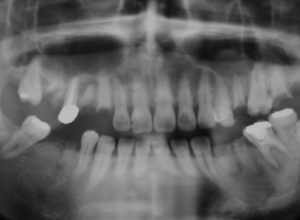

初診時のレントゲン写真。

治療後3年経過。適切な根管治療を行い、咬み合わせを再構築しました。